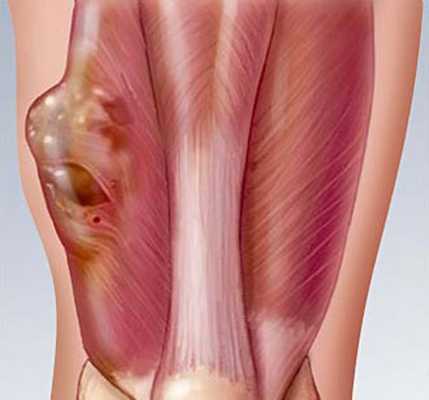

— Осмотр опытного специалиста, врача-онколога; На фото можно увидеть, как выглядит саркома мягких тканей: